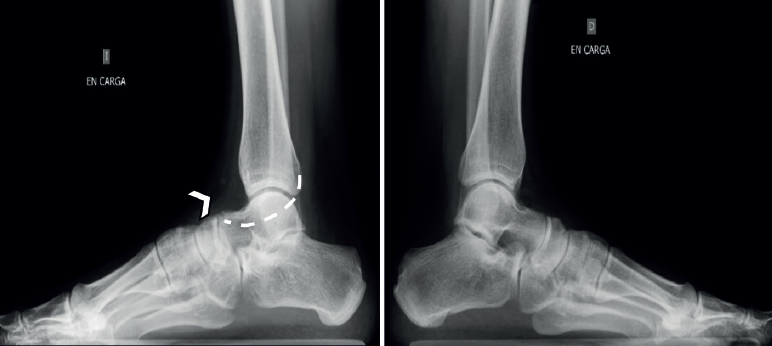

Las radiografías simples deben ser siempre bilaterales. Se deben solicitar: anteroposterior (AP) en carga, lateral en carga y oblicua a 45°. La radiografía a 45° descrita por Sloman en 1921(39) demuestra la presencia de coaliciones CN en el 90-100% de los casos(40,41). Es cierto que la superposición de los huesos del tarso dificulta el diagnóstico de la coalición, pero se han descrito algunos signos distintivos directos e indirectos que ayudan al diagnóstico, siendo los más conocidos el signo del oso hormiguero, el pico del astrágalo (talar beak) y el signo de la C. Estos signos clásicos muestran una buena especificidad, pero una sensibilidad moderada: el hecho de que la coalición sea fibrosa, cartilaginosa u ósea, y el tamaño variable de la coalición influirán en la imagen y en nuestra capacidad de diagnóstico.

El hocico del oso hormiguero es diagnóstico de una coalición CN. Inicialmente descrito en las radiografías oblicuas, también puede ser visible en las proyecciones laterales(37,42,43)(Figura 6A). El proceso anterior del calcáneo normalmente es triangular, pero se alarga en las coaliciones y la punta es cuadrada como el hocico de un oso hormiguero. Un estudio de Crim y Kjeldsberg(22) demostró en radiografías laterales una sensibilidad del 72% y una especificidad del 90% del signo del oso hormiguero, y del 90-100% de los casos en las oblicuas(40,41). Será incompleta en caso de fibrocartilaginosa y completa en las uniones óseas.

El hocico del oso hormiguero inverso: en la radiografía AP en carga del pie, se verá el proceso lateral del escafoides más alargado (Figura 6F, flecha). Normalmente los márgenes están alineados con la cabeza. En las coaliciones, el borde lateral tiende a estar más alargado (Figura 6B, asterisco), en algunos casos su borde es cuadrado y parece articular con el calcáneo. La sensibilidad original reportada de este signo fue del 50% y la especificidad fue del 100%(22), aunque un informe posterior encontró una sensibilidad de tan solo el 18%(44).